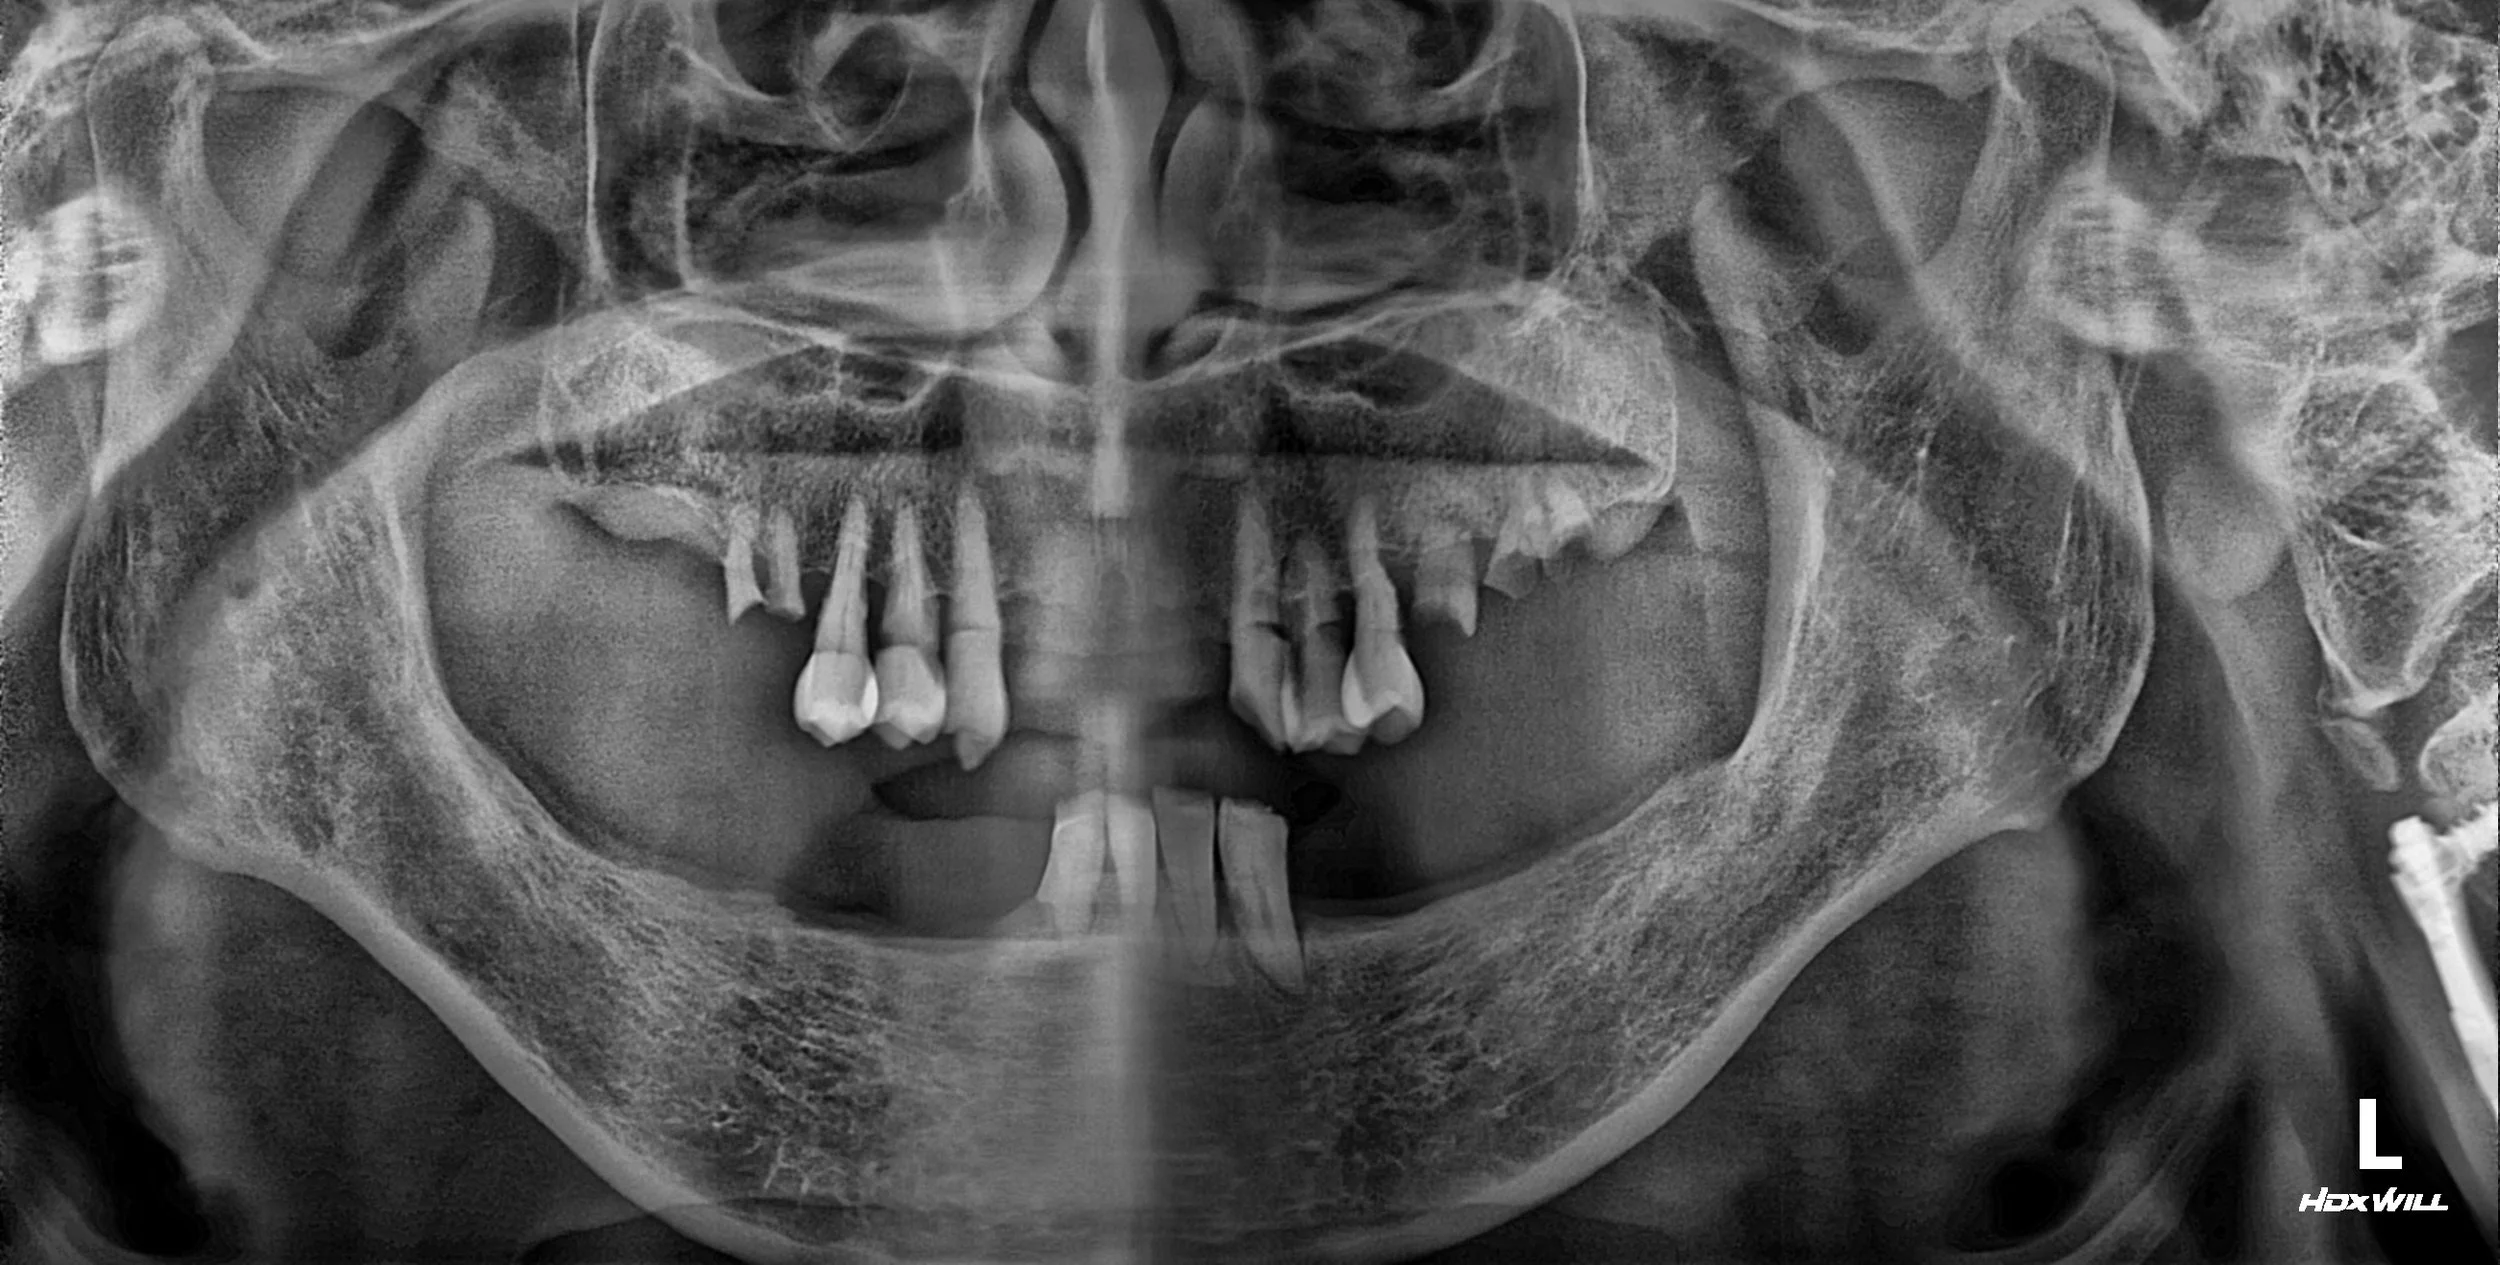

OPG - BEFORE